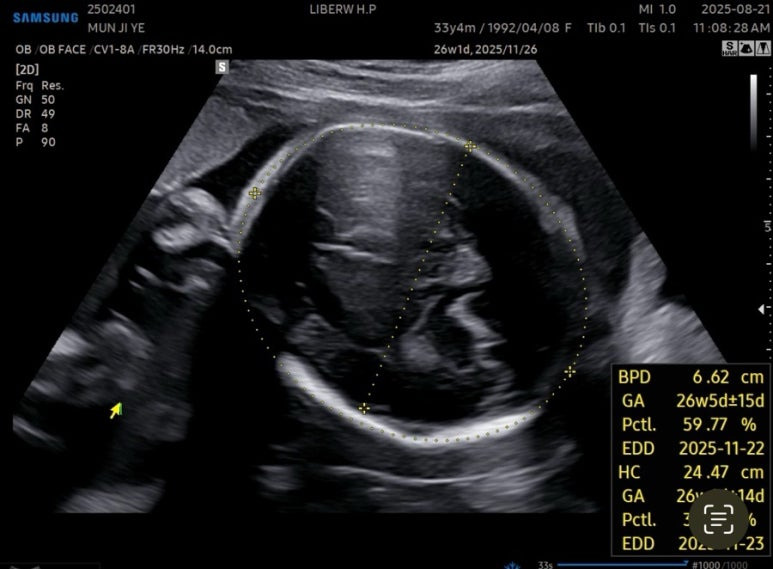

27주차 사탕이는

머리둘레 6.62cm

배 둘레 22.91cm

다리길이 4.61cm

몸무게 956g

심장박동수 150bpm

경부길이 3.44cm

양수량도 적당했다